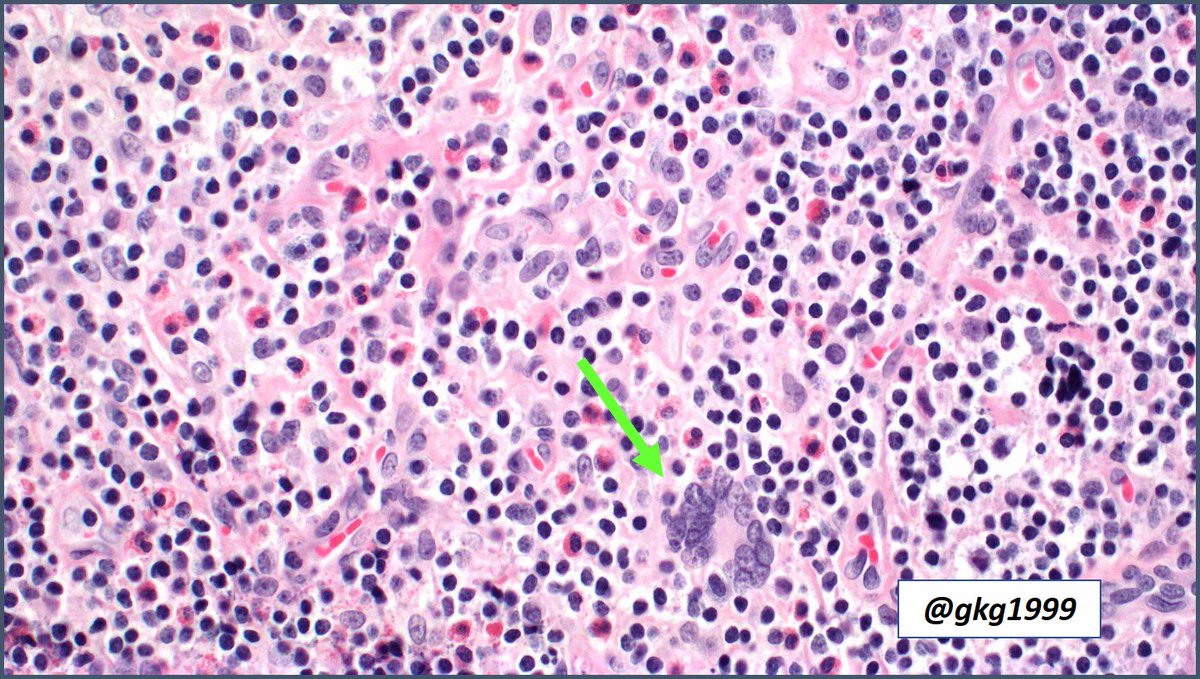

Kimura disease, Warthin-Finkeldey Cells #pathology #pathologists #hemepath #pathboards